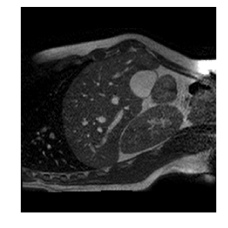

Qualitative results are shown in Fig. 4. We observe no large qualitative differences in the performances of MFIN and MFINc for either loss function. Since, MFINc-SSIM provides the best quantitative results, we show interpolated images from this method and compare them against SCIN-SSIM. Both methods perform well when the motion between the neighbouring images is low. This is reflected in the absence of any structures in the error images in Fig. 4.1. However, RMSE is lower for SCIN because it produces a denoised interpolated image, while MFIN carries over the noise pattern from the neighbouring known image. Whenever there exists high motion between the images being interpolated, SCIN produces blurry images and often misses image structures. This can be observed in cases 2-4 in Fig. 4. For all these cases, MFINc (and also MFIN) produces sharp images and largely preserves structures in the images. Fig. 4.2 shows a case where MFINc additionally has a much better performance with respect to image alignment. Fig. 4.3 shows a representative case, with small improvement in image alignment, yet worse RMSE and SSIM values for MFINc. Finally, Fig. 4.4 shows a case, where MFINc produces worse alignment of structures than SCIN.

1)

14.13, 0.81 13.02, 0.84

2)

9.16, 0.76 10.12, 0.74

3)

9.75, 0.85 12.94, 0.81

4)

a b c d e